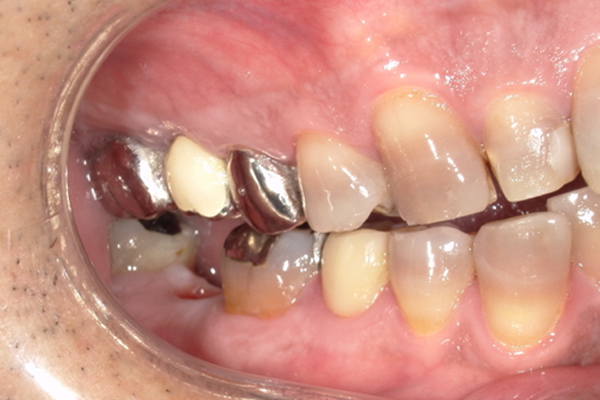

| 主訴 | 右下の奥歯が痛い |

|---|---|

| 治療内容 | 右下奥歯が割れていたため抜歯、その後インプラント治療を行った。(左の写真は抜歯後の写真) |

| 治療期間 | 4ヶ月 |

| 治療費 | 41万5千円 |

| 治療 リスク | 抜歯後インプラントの処置まで3ヶ月程度治癒期間(骨ができるまでの期間)が必要なことがあります。 |